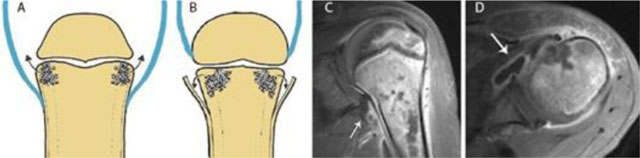

Figure 8

Joint contamination in osteomyelitis. Schematic drawings (a) and (b), coronal (c) and axial (d) T1–WI Fat–Sat after gadolinium contrast administration. (a) shows a joint in which the joint capsule (blue) is attaching underneath the growth plate. This intra-articular location of the growth plate may lead to rapid spread of infection into the adjacent joint. (b) shows a joint in which the joint capsule (blue) is attaching above the growth plate. An extra-articularly located growth plate protects against early joint contamination. (c, d). Example on MRI of a patient with rapid spread of the infectious focus to the adjacent left shoulder joint. Because the joint capsule of the shoulder insert below the growth plate, metaphyseal osteomyelitis may easily spread through the medial cortex directly into the joint resulting in synovial enhancement (white arrow).